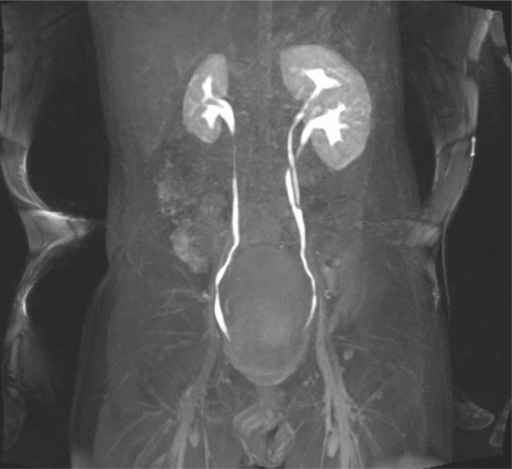

Comparison Of Intravenous Pyelogram Or Ivp Is An Xray Exam Of Urinary …

IVU shows partial obstruction at left ureter due to a s | Open-i

I.V.P is an X-ray Exam of Urinary Tract after Injection Contrast Media …

X-ray images of the kidney, ureter, and bladder. (A) Pretreatment …

A bifid ureter is formed when there is a duplex kidney (separate …

Incomplete double ureter | Radiology Case | Radiopaedia.org | Radiology …